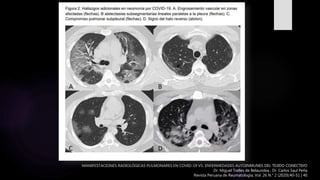

MANIFESTACIONES RADIOLÓGICAS PULMONARES EN COVID-19 VS. ENFERMEDADES AUTOINMUNES DEL TEJIDO CONECTIVO

Dr. Miguel Trelles de Belaundea , Dr. Carlos Saul Peña

Revista Peruana de Reumatología, Vol. 26 N.° 2 (2020):40-51 | 40

El COVID-19 típicamente induce una neumonía bilateral

difusa intersticial con lesiones en distribución asimétrica y

parcheada que afecta principalmente a la periferia pulmonar.